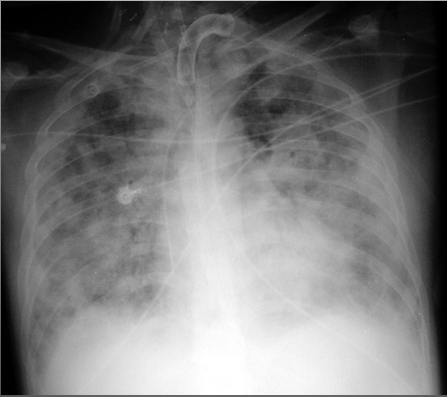

What’s your diagnosis?

Right upper lobe pneumonia